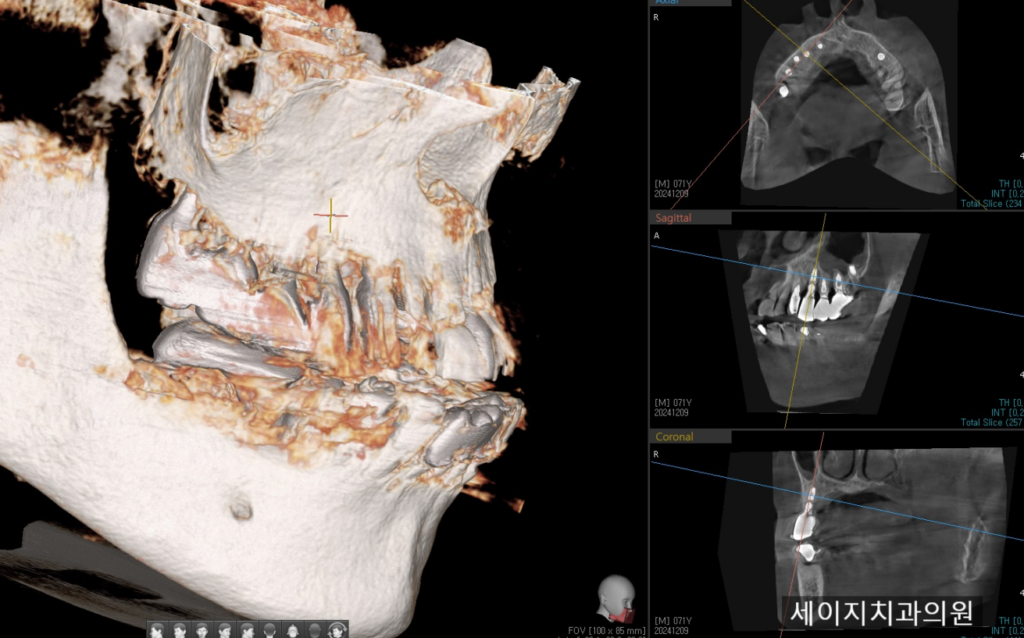

24. 12. 09(CBCT를 이용한 임플란트 제거 계획)

먼저 CT를 이용하여 임플란트의 부러진 뿌리 제거시 접근 방법을 찾아보았습니다. 임플란트 뿌리파편을 감싸고 있는 뼈와 잇몸은 온전한 상태였기에 접근을 위하여서는 주변부의 삭제를 계획하였습니다.

완전히 매복된 사랑니를 뽑는다는 생각으로 계획을 하였고, 주변부의 일부 골편을 삭제하는 계획을 하였습니다. 뼈안에 박혀있는 금속편을 제거하기 위해서는 정교한 접근이 필요하고, 추후 임플란트 수복을 위해서는 너무 많은 골삭제는 지양해야 하기 때문에 CT를 이용하여 모의 수술을 해보았습니다.